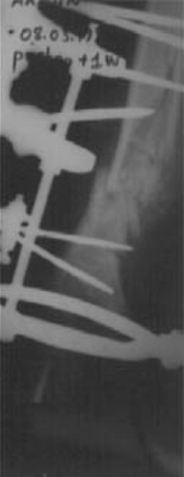

8. HASTA KOMFORU AÇISINDAN SON YILLARDA UNİLATERAL (TEK TARAFLI) EXTERNAL FİXATÖRLER KULLANARAK HASTANIN GÜNLÜK YAŞAMDAKİ SIKINTISINI AZALTMAKTAYIZ.